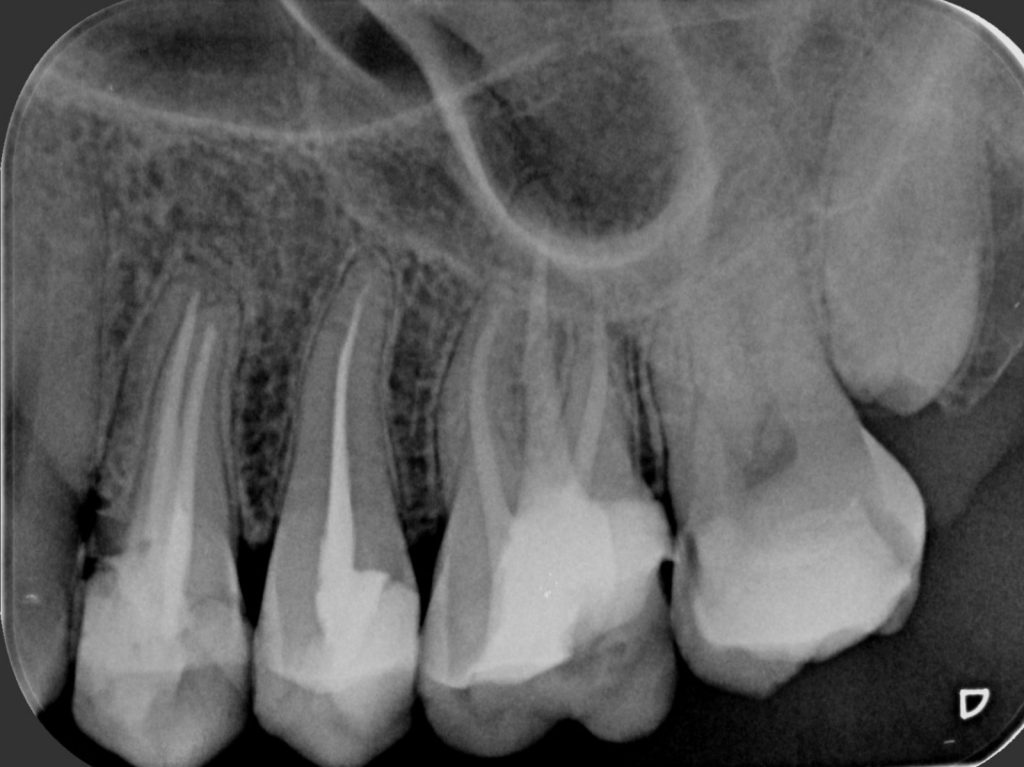

Dentalni radiogram

Retroalveolarni ili “mali” snimak je najčešći tip snimanja zuba i predstavlja ciljani snimak jednog, dva ili tri susedna zuba. Pruža precizne i detaljne informacije o stanju celog zuba:  krunice, njegovog korena i okolnih struktura. Decenijama je nezamenljiv u dentalnoj dijagnostici.

Prednosti digitalnog snimanja u odnosu na tradicionalno:

• Višestruko niža doza zračenja za pacijenta

• Softverska obrada snimka daje bolju rezoluciju i kvalitetniji snimak

• Snimak se u digitalnom formatu može slati na e-mail i viber, narezati na CD ili odštampati na film foliji.